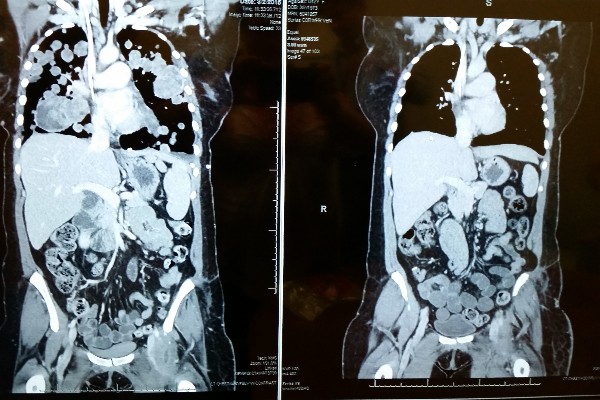

Now she is in the fight of her life. A fight for her life and she needs your help. Her path started on September 19th when she was diagnosed with Soft Tissue Sarcoma. The tumor was in the psoas muscle of her left leg. She received chemotherapy and was scheduled for radiation, but before that could happen it grew too fast and too large, so it was decided to remove it from her and within days she was off to surgery. The surgery was a success and the tumor removed. There were setbacks including a severe infection in the surgery site which extended her hospital stay to almost 3 weeks and delayed her next chemotherapy treatments. After a month of delays, we found out that her cancer had spread to her lungs and had grown so fast that her breathing was compromised. Her doctor decided to try another round of chemotherapy to try to shrink or slow the progression of the tumors in her lungs. It did not work. The cancer did not respond.

We traveled to Denver for what ended up being 6 weeks. When we arrived Nichol was up to 5L/hour of oxygen and in a wheelchair due to the extreme weakness the Cancer had caused and the elevation of the city itself. What we experienced in Denver was no less than a miracle. After less than 2 weeks on the study drug Nichol was able to reduce her oxygen use to 2L/hour and was out of the wheelchair except for long walks, after 4 weeks she only used it when she slept or was out walking being completely out of the wheelchair. By the time we return to Oregon she was off oxygen completely and other than her nearly bald head looked as if she'd never been sick. The study drug has worked better than we could have hoped! Thank you all for your help to get us to Denver. Without you we very well could have lost her.

The way that this drug works, Nichol will have to be on it for the rest of her life in order to suppress her cancer. For this to happen she has to travel to Denver every 4 weeks for blood work and other tests such as CT scans. With the cost of airfare, food, and other expenses on top of the cost of her medical care it has put our already stretched budget under some serious strain.